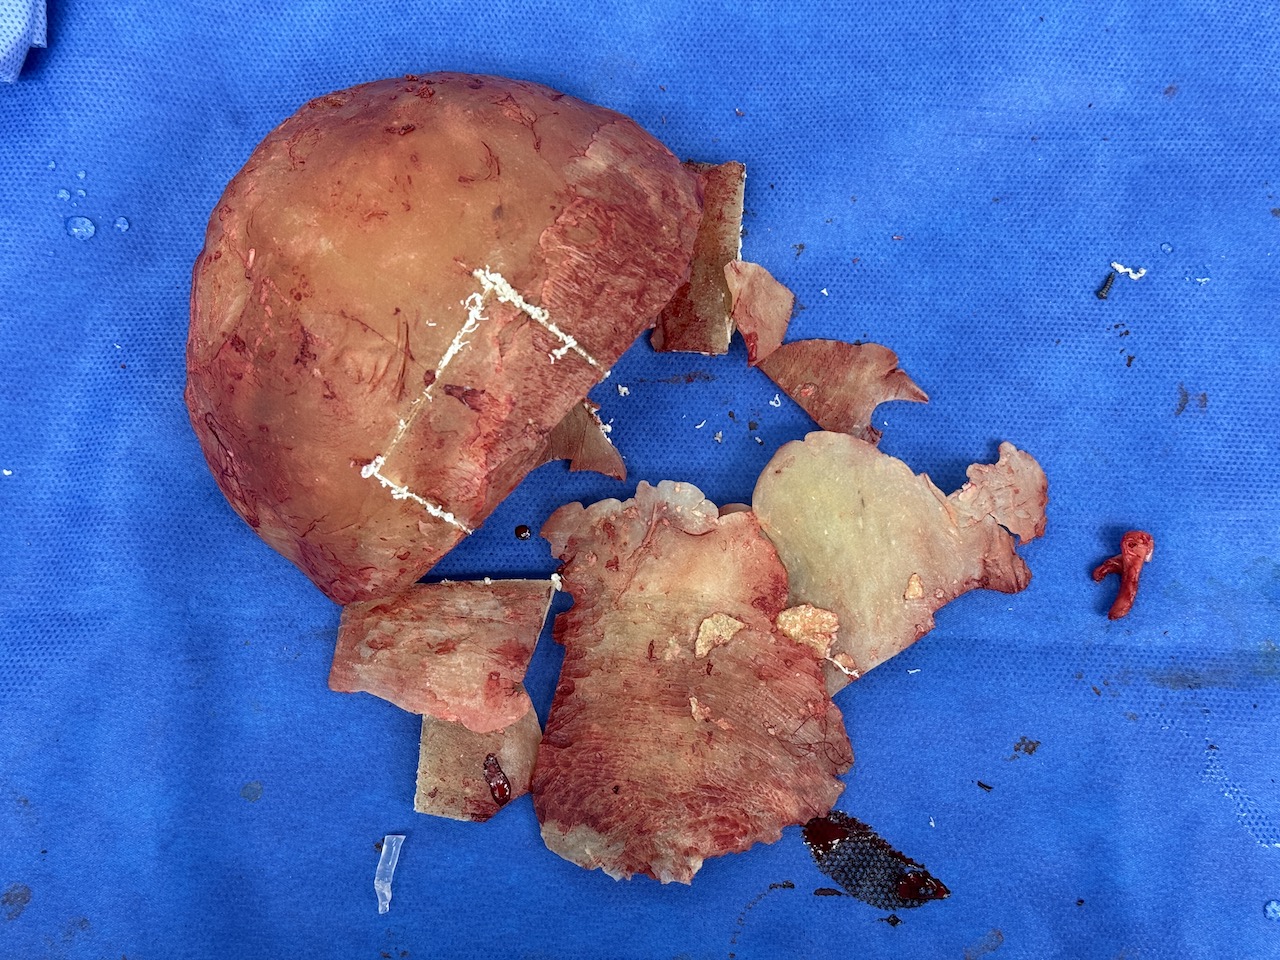

Severe narrowing skull deformity from prior sagittal craniosynostosis repair as an adult.

Complete replacement of entire skull by a custom implant with temporal fat injections.

Severe narrowing skull deformity from prior sagittal craniosynostosis repair as an adult.

Complete replacement of entire skull by a custom implant with temporal fat injections.